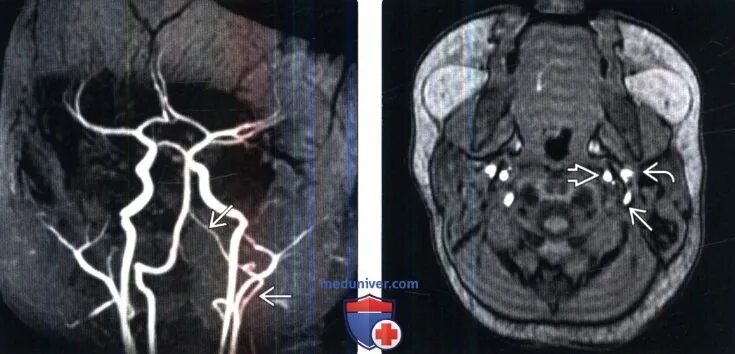

Асимметрия кровотока по интракраниальным сегментам